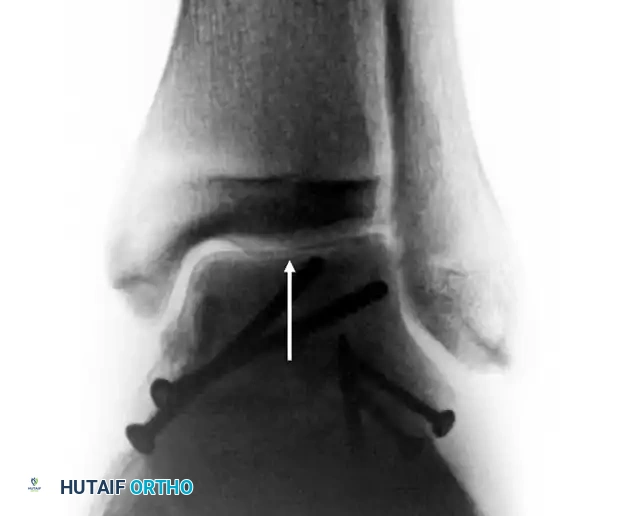

Final Verification

- Check the final position with intraoperative fluoroscopy.

- Obtain a Canale view to definitively rule out varus malreduction.

- If the medial malleolus was osteotomized, reduce it anatomically and fix it with two parallel partially threaded cancellous screws.

Between 6 and 8 weeks post-injury, an AP radiograph of the ankle should be scrutinized for the Hawkins sign.

* Positive Hawkins Sign: A thin line of subchondral radiolucency (atrophy) along the dome of the talus. This indicates that the bone is vascularized enough to undergo disuse osteopenia. It is a highly sensitive indicator that AVN will not occur.

* Negative Hawkins Sign: If the bone remains dense and sclerotic relative to the surrounding osteopenic bone, osteonecrosis is likely present.